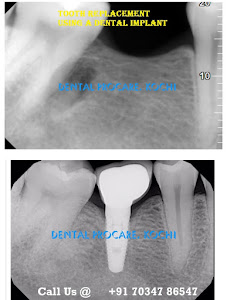

Welcome to our gallery

See how our company transforms ideas into reality. This gallery is a visual testament to our work and achievements.